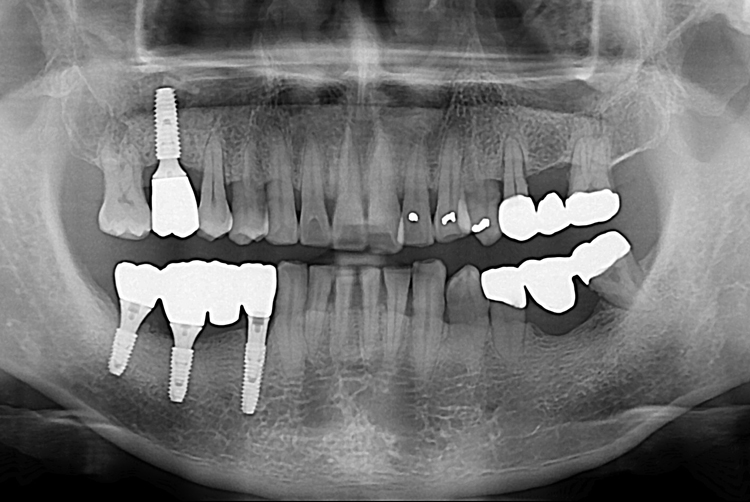

[임플란트] 어금니 임플란트

치료후 : 2017-08-08

세종치과는 많은 환자와 다양한 케이스를 바탕으로

항상 편안한 임플란트 수술을 제공하고자 노력하고,

오래동안 튼튼히 쓸 수 있는 임플란트 수술을 가장 큰 목표로 삼고 있습니다.